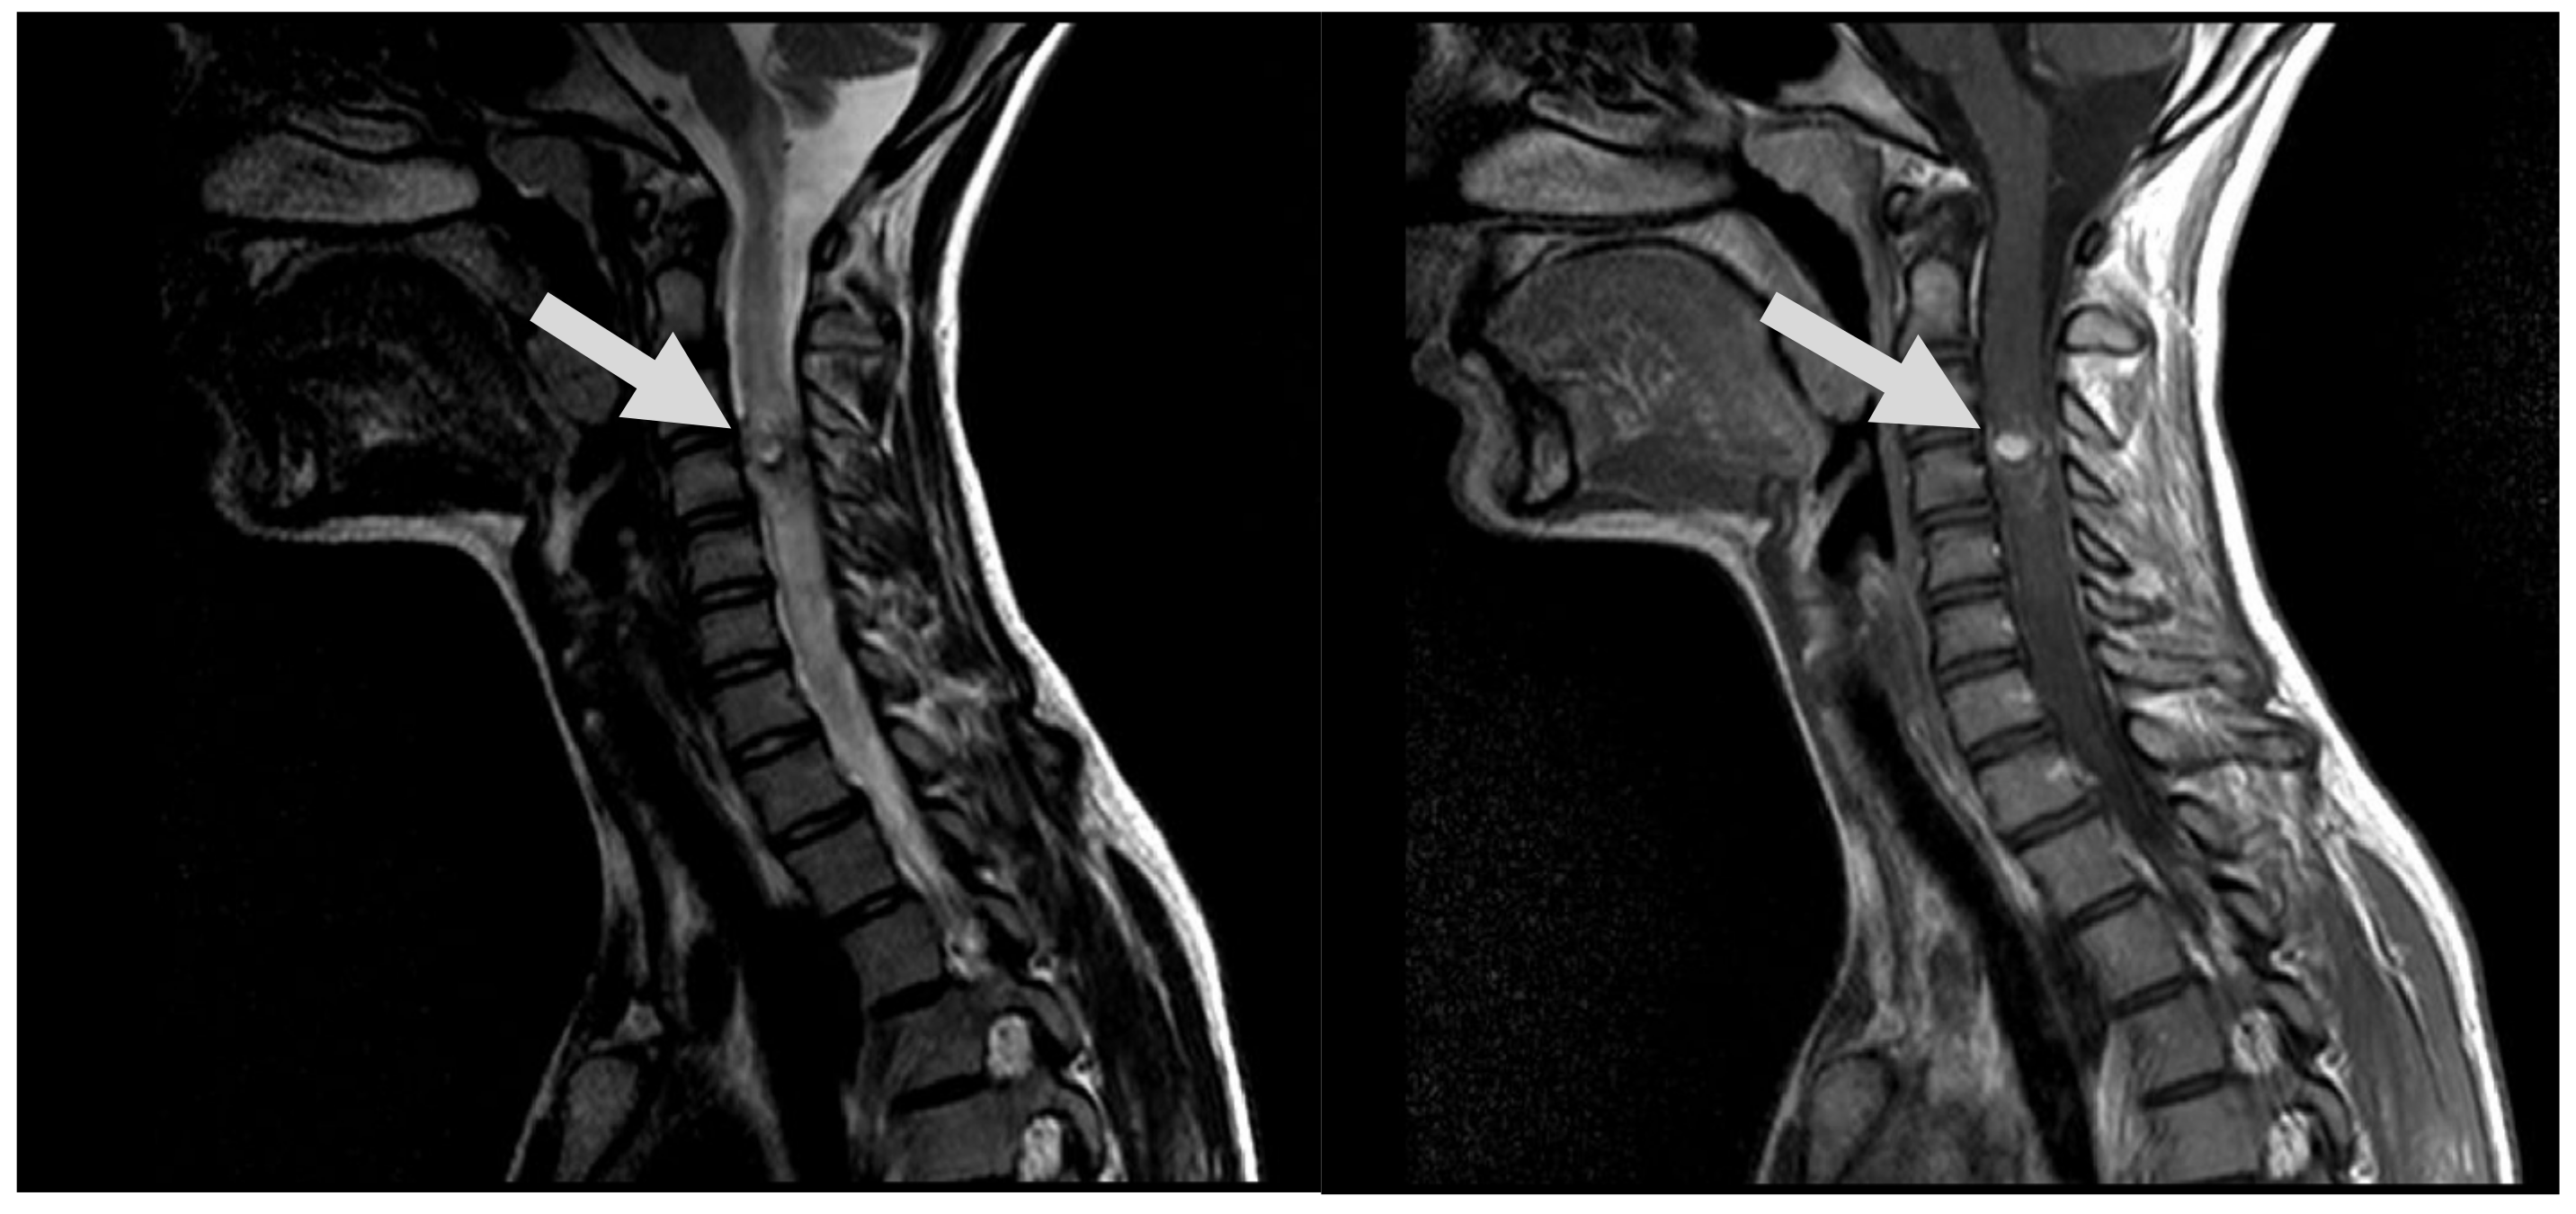

7.1. First Episode (2011)

7.2. Second Episode (2020)

7.3. Third Episode (2023)